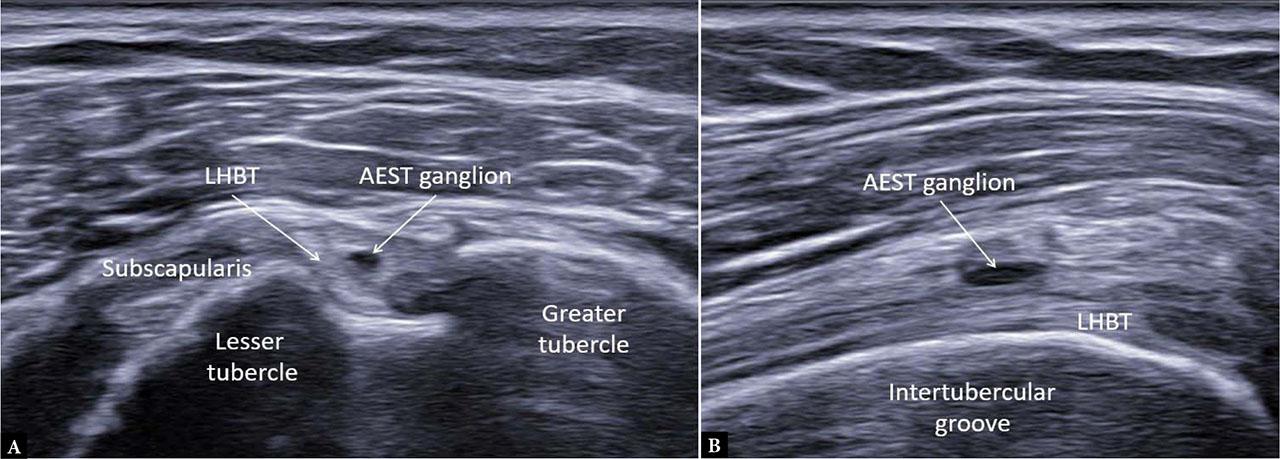

Among the 3,600 shoulder ultrasound examinations, 23 cases were initially suspected of AEST pathology. After detailed review, four cases were excluded: one due to a thin hyperechoic fibrous band within a degenerative LHBT mimicking a bifid tendon (Fig. 5), two cases in which normally echogenic fibers were preserved despite advanced LHBT degeneration (Fig. 6), and one case of hypoplastic LHBT (Fig. 7).

Pseudo-double long head of the biceps tendon (LHBT). A. Longitudinal view mimicking a bifid tendon. B. Transverse view showing a narrow intratendinous fibrous band accentuated by degenerative changes

Small intra-aponeurotic ganglion in the left shoulder. A. Transverse view of aponeurotic expansion of the supraspinatus tendon (AEST). B. Longitudinal view (AEST–supraspinatus classification: Ia, case 19)